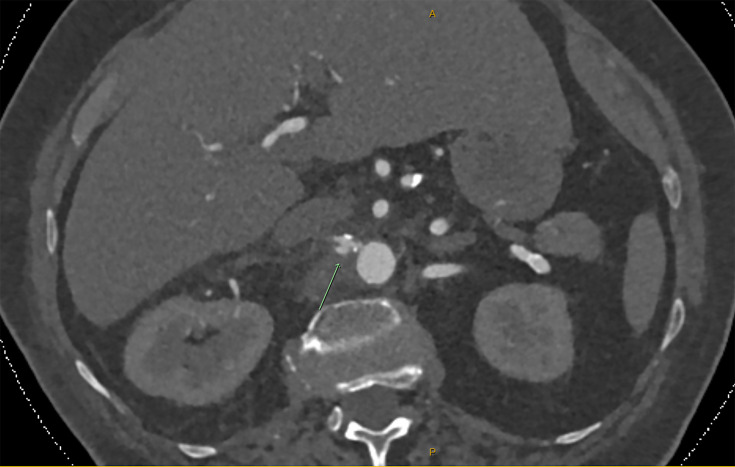

Staphylococcus pseudintermedius is a common commensal and opportunistic canine pathogen with emerging pathogenicity in humans. We describe the first case of invasive S. pseudintermedius infection causing aortitis and mycotic aneurysm in an 83-year-old patient, treated successfully with flucloxacillin. This case highlights the potential for S. pseudintermedius to cause serious endovascular infection in humans.